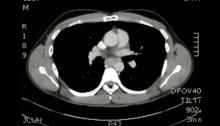

VATS can be safely used for dissection of masses in the visceral mediastinum. This video presents the case of a 31-year-old man diagnosed with a metastatic germ cell tumor, and successfully treated with a three-port posterior approach VATS.